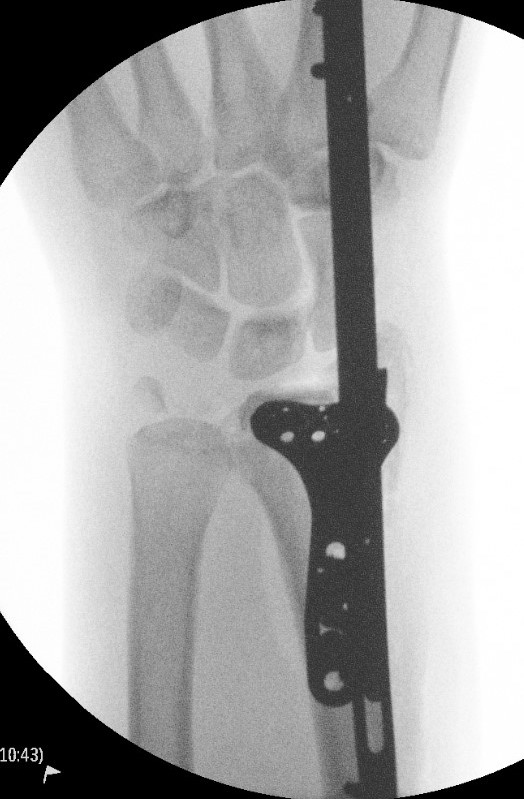

Dorsal distraction plating

Indication

Internal radiocarpal distraction

- unreconstructable distal radius fractures

- early weight bearing in poly trauma patients

- osteoporotic bone

Advantage - no pin site infection from external fixation

Disadvantage - need to remove plate at 3 - 4 months once fracture united

Technique

AO surgery foundation extended dorsal approach wrist

AO surgery foundation dorsal distraction plate

Arthrex dorsal spanning plate 2 incision video

Extended dorsal approach

- protect sensory radial nerve

- open 3rd extensor compartment / retract EPL radially

- mobilized 4th extensor compartment / retract EDC ulnarly

- bare area of radius proximally between EDC and ECRB / ECRL

Fixation to 2nd or 3rd metacarpal first

- 2nd metacarpal: under 2nd extensor compartment

- 3rd metacarpal: under 4th extensor compartment

- reduce / distract joint

- +/- additional radius fixation